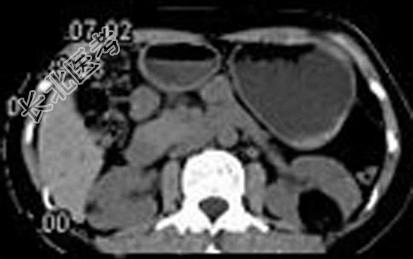

- 多项选择题女,38岁, 体检时B超在左肾探及一中强回声光团,边界清, 内部回声均匀,CT检查如图所示, 下列说法正确的是 ( )

A、左肾中部靠后方可见一类圆形低密度病灶

B、病灶与周围肾组织界限清楚

C、病灶密度为脂肪密度

D、考虑为左肾血管平滑肌脂肪瘤